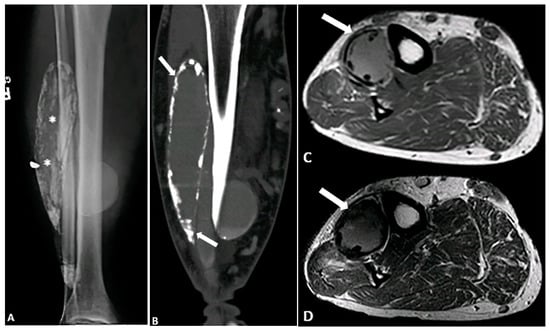

5.5. Calcific Myonecrosis

- O’Dwyer, H.M.; Al-Nakshabandi, N.A.; Al-Muzahmi, K.; Ryan, A.; O’Connell, J.X.; Munk, P.L. Calcific myonecrosis: Keys to recognition and management. Am. J. Roentgenol. 2006, 187, W67–W76. [Google Scholar] [CrossRef]